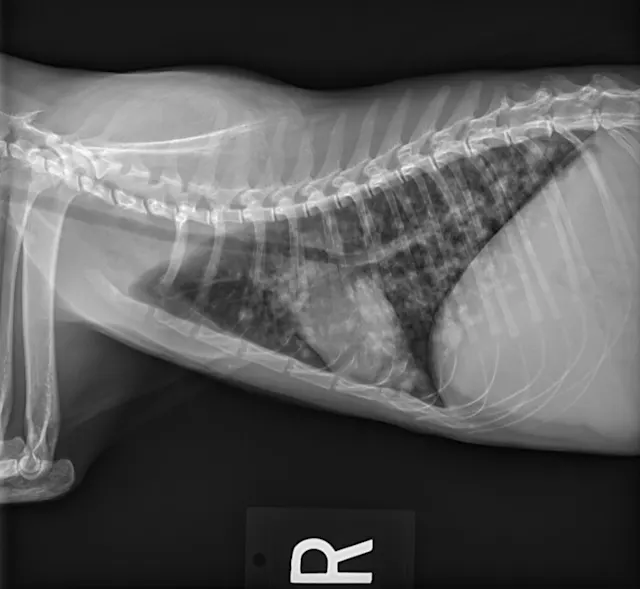

At the 1-month recheck, her weight had increased to 6 lb (3 kg); estimated BCS was 3/9. Physical examination showed a normal respiratory pattern, but increased bronchovesicular sounds were still present bilaterally. No fundic abnormalities were noted. Radiographs indicated subtle improvement of the diffuse nodular pulmonary pattern (Figure 2).

FIGURE 2 Left lateral (A), right lateral (B), and ventrodorsal (C) thoracic radiographs 1 month after initiation of itraconazole. Subtle improvement of the diffuse nodular pulmonary pattern can be seen.